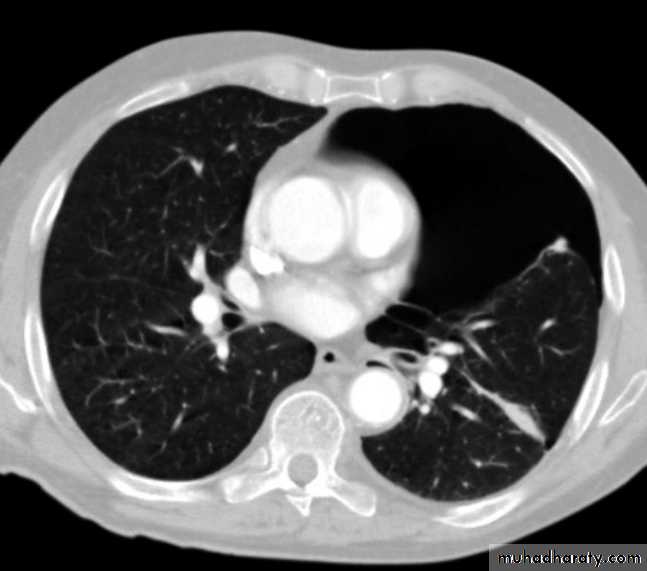

Hydatid cystAppear as large oval hypo dense area density of fluid with well defined margin , sometime at their periphery multiple flecks of calcification are seen at their periphery .

Hydatid cyst with daughter cyst , appear as multiple hypo densities rounded area within the main loculi with multiple rim of

calcification

Hydatid cyst within the liver